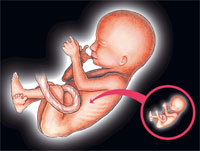

Se da en uno de cada 500.000 nacimientos y se conoce en términos médicos como ‘fetus in fetu’. Ha sido en Hong Kong (China) donde se ha diagnosticado el último caso de este acontecimiento tras encontrársele a una bebé de tres semanas dos fetos de mellizos en el vientre. El ‘fetus in fetu’ suele producirse por un fallo en la formación del cigoto antes de la formación del embrión, lo que conlleva que rara vez tenga órganos internos funcionales. En el caso aparecido en China, los fetos, de ocho y diez semanas de gestación, tenían formadas las piernas, los brazos, la columna y parte de los intestinos.

En declaraciones a ‘Mirror’, el Dr. Yu Kai-man, especialista en ginecología y obstetricia, ha señalado que la concepción natural por parte de la bebé es imposible. «Los gemelos son de los padres. Lo que ocurrió es que, simplemente, el proceso de fertilización ocurrió por el lado equivocado».